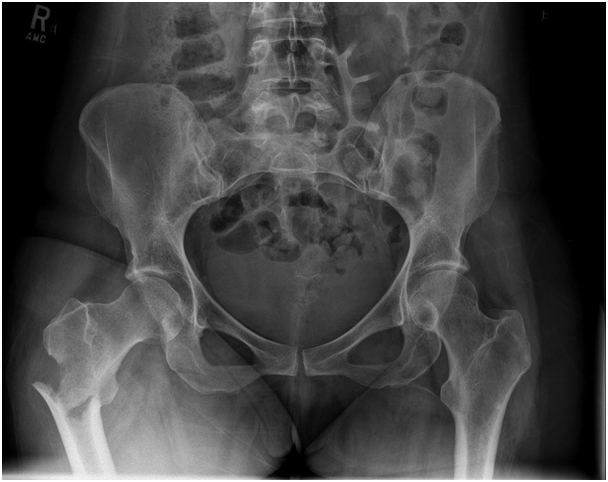

A 79-year old female presents with complaints of right hip pain for 2 months. She denies prior injury or precipitating event. The pain is made worse by lying on the affected side and occasionally hurts with hip motion. The pain is improved with NSAIDS and placing ice on the lateral aspect of her hip. Her primary care physician ordered x-rays which showed a bone lesion in the proximal femur. Her PCP was concerned she had bone cancer and ordered an MRI of the thigh to further evaluate. AP x-ray and a coronal MRI image are shown above. The patient denies a history of weight loss, fatigue, and history of cancer. On exam the patient has no pain with passive range of motion of the hip in all planes. She has pain with palpation over the greater trochanteric bursae. Motor and sensation are intact throughout the lower extremities. What is the most likely cause of this patient’s pain?